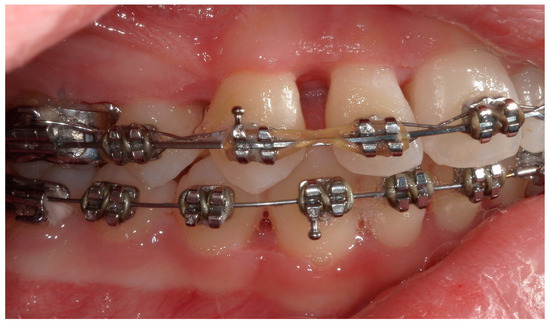

4.2. Case 2